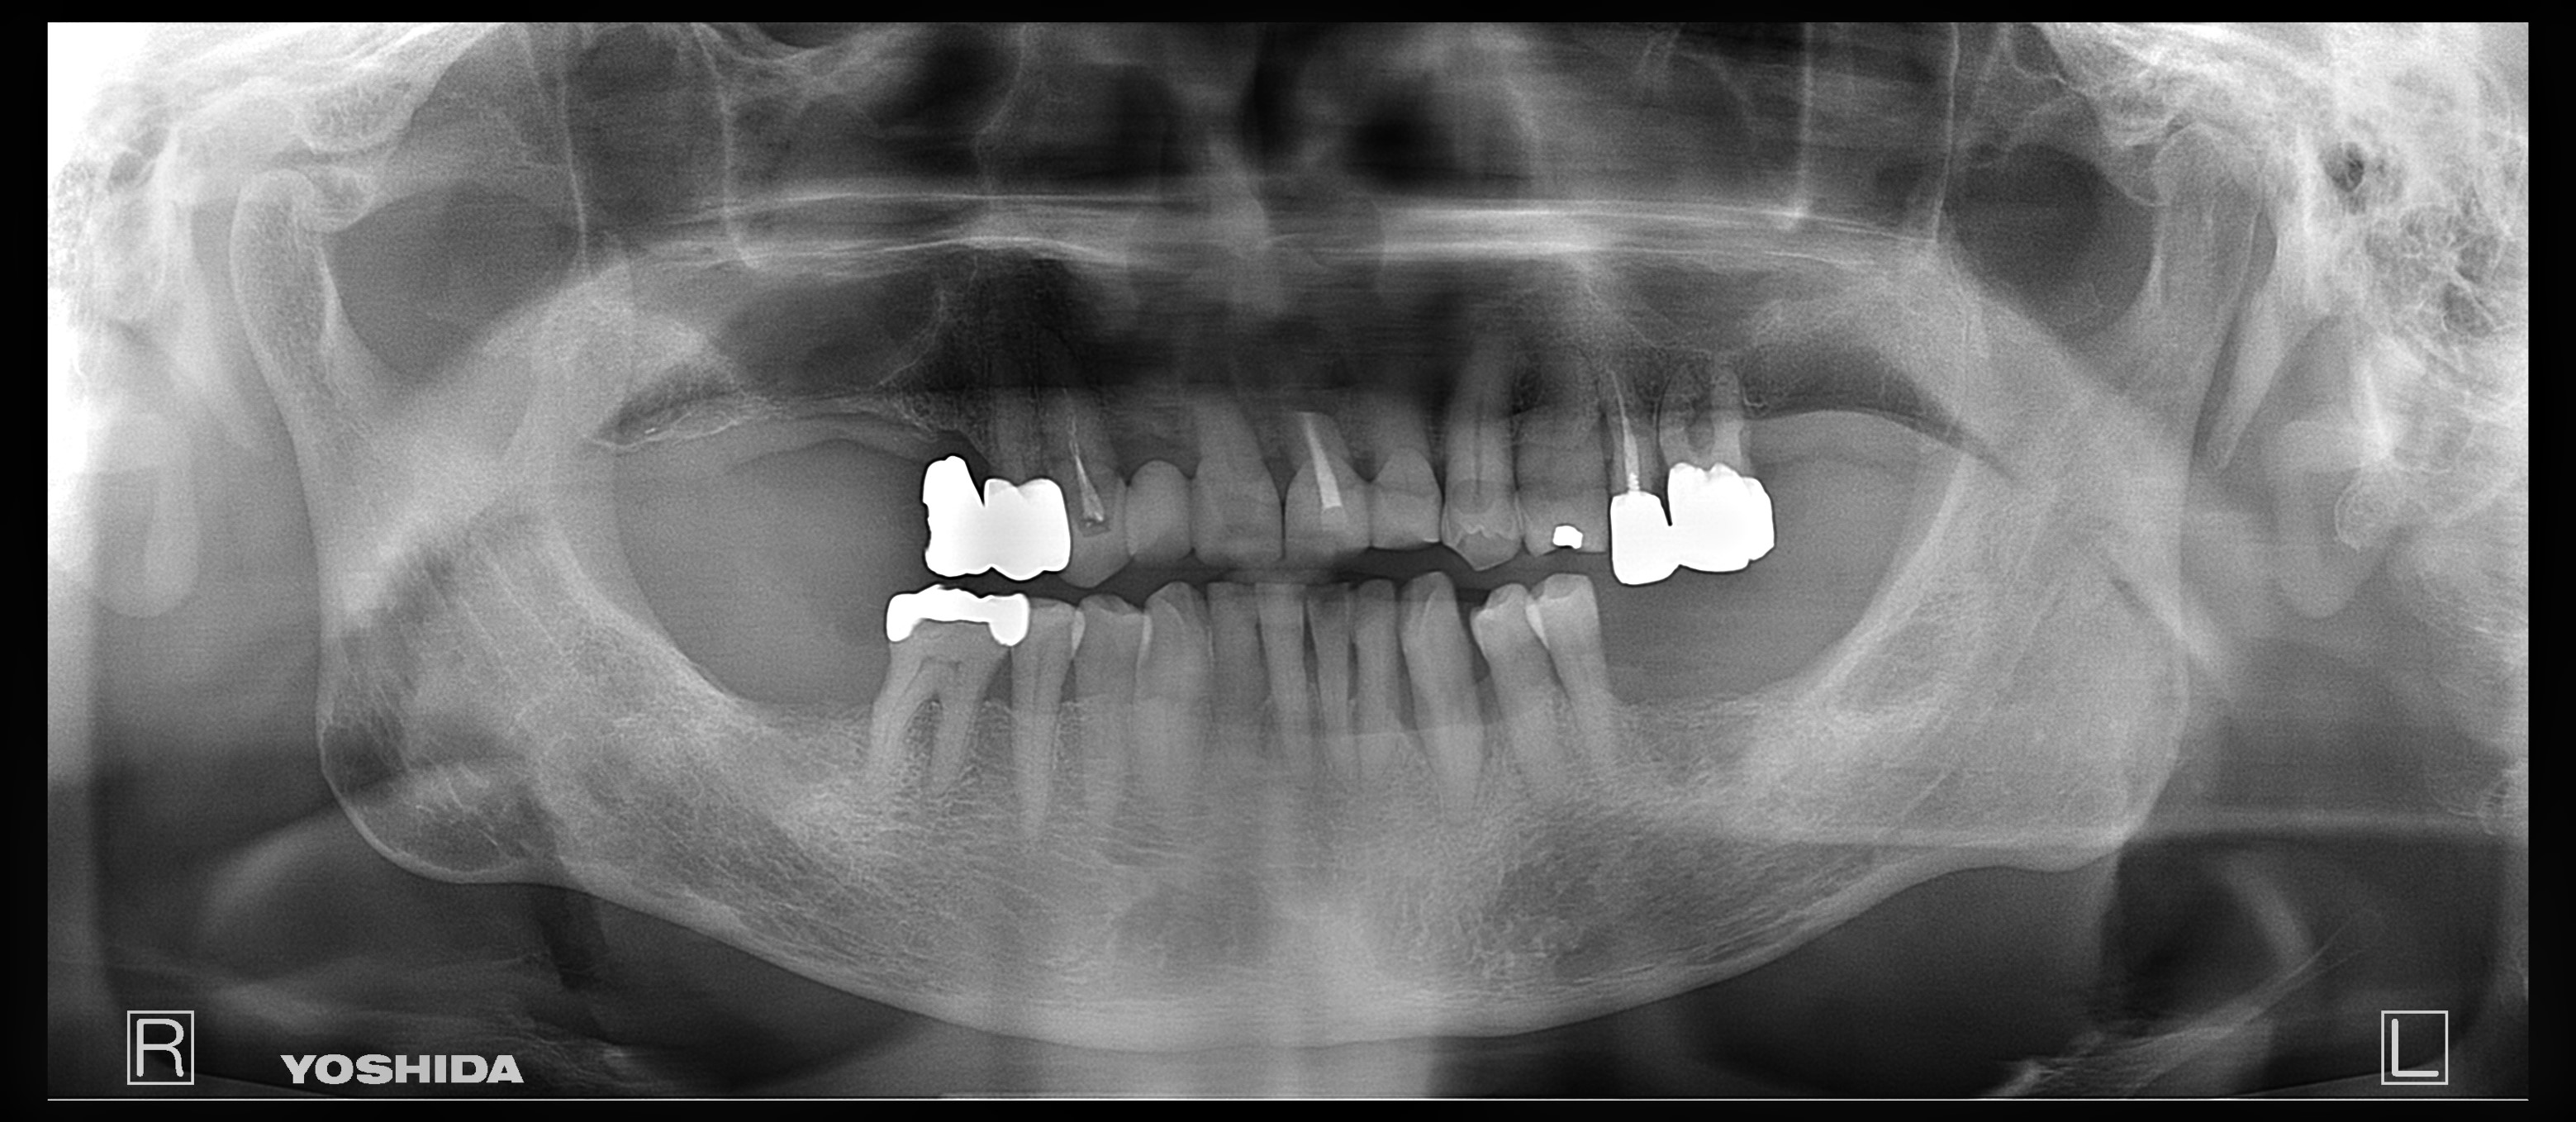

父のレントゲン写真と口腔内を見て、インプラントを入れる位置を一緒に決めて行きました。

右上は歯があるように見えて隣の歯につなげてある被せ物があるだけの状態です。

その右上は骨がないためサイナスリフトという処置を施した後にインプラントを入れる手術をしなければならないのですが、(サイナスリフトは骨を作るだけで6ヶ月待ちます。)

私は水口先生が開発したオステオプッシャーを用いて、骨がないところに骨を足す手術と並行してインプラントを入れる手術を施しました。

左側の入れ歯を入れていたと言っている場所には通常の方法でインプラント治療を、左上の奥歯2本は歯周病でグラグラだったため抜歯と同時にインプラントと治療を行いました。

左側のレントゲンがが最初の状態です。右側がインプラントを入れ、被せ物まで入れた状態のレントゲンです。